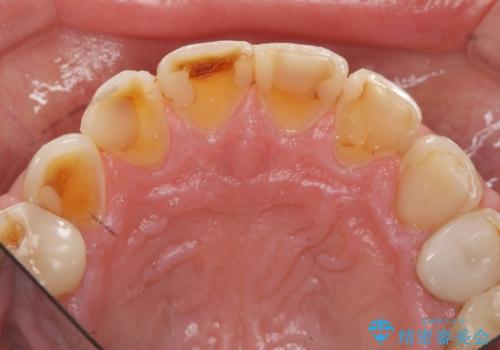

歯ぎしりですり減った 前歯の見た目を回復したい

- 歯ぎしり・嘔吐症により歯がすり減ってしまい、色調・見た目を改善したいと来院されました。